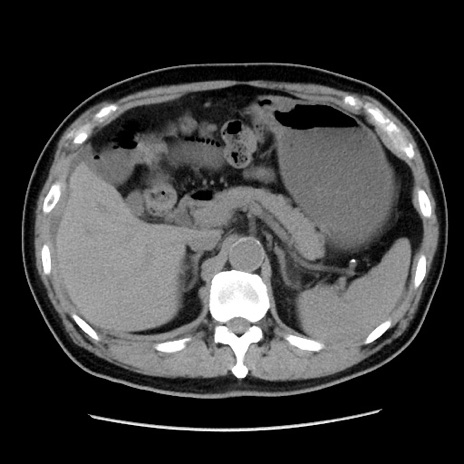

症例16(横断像)

【症例】 70歳代男性

【主訴】 腹痛、嘔吐

【現病歴】 約1ヶ月前より間欠的に腹痛と嘔吐あり、当院消化器内科を受診したところCTで多発する肝臓のLDAを指摘され、精査中であった。以降は消化器症状は安定していたが、2日前より嘔気と腹痛があり、同日より排便・排ガスが消失した。改善認めず、 本日、救急外来を受診した。

【既往歴】 大腸ポリープ切除後。

【身体所見】意識清明・会話良好、BT 36.3℃、BP 127/80mmHg、 P 80bpm、腹部:膨満あり、平坦・軟、上腹部正中および下腹部正中に圧痛あり、反跳痛なし、筋性防御なし。

【データ】WBC 7200、CRP 0.77